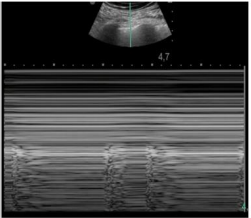

Caso clínico para responder à questão.

Um paciente de 50 anos de idade encontra-se, internado na UTI por conta de choque séptico de foco pulmonar, em ventilação mecânica na modalidade pressão e no modo assisto-controlado. Pela manhã foi submetido a acesso venoso central em veia axilar guiado por ultrassonografia. Ao exame físico, notou-se que o paciente está com hipotensão e taquicardia. A primeira hipótese diagnóstica é pneumotórax e é realizada radiografia com imagem apresentada.